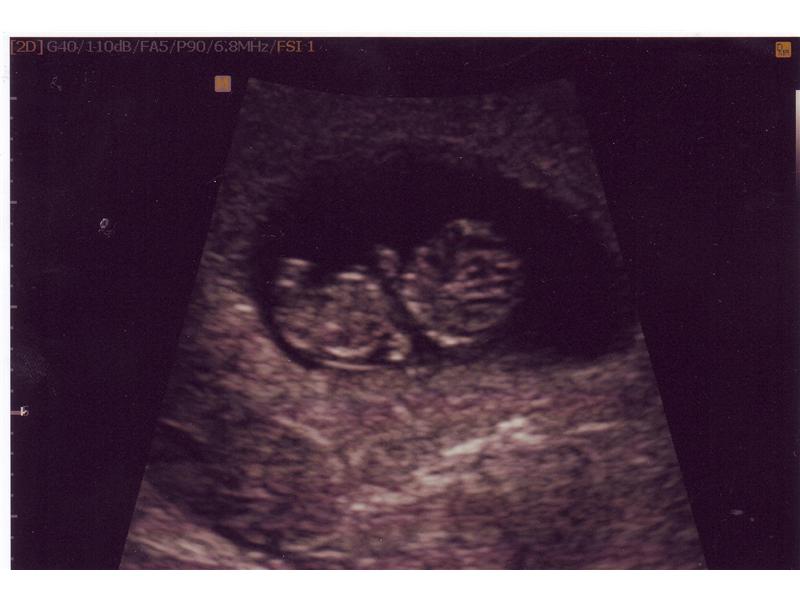

utz